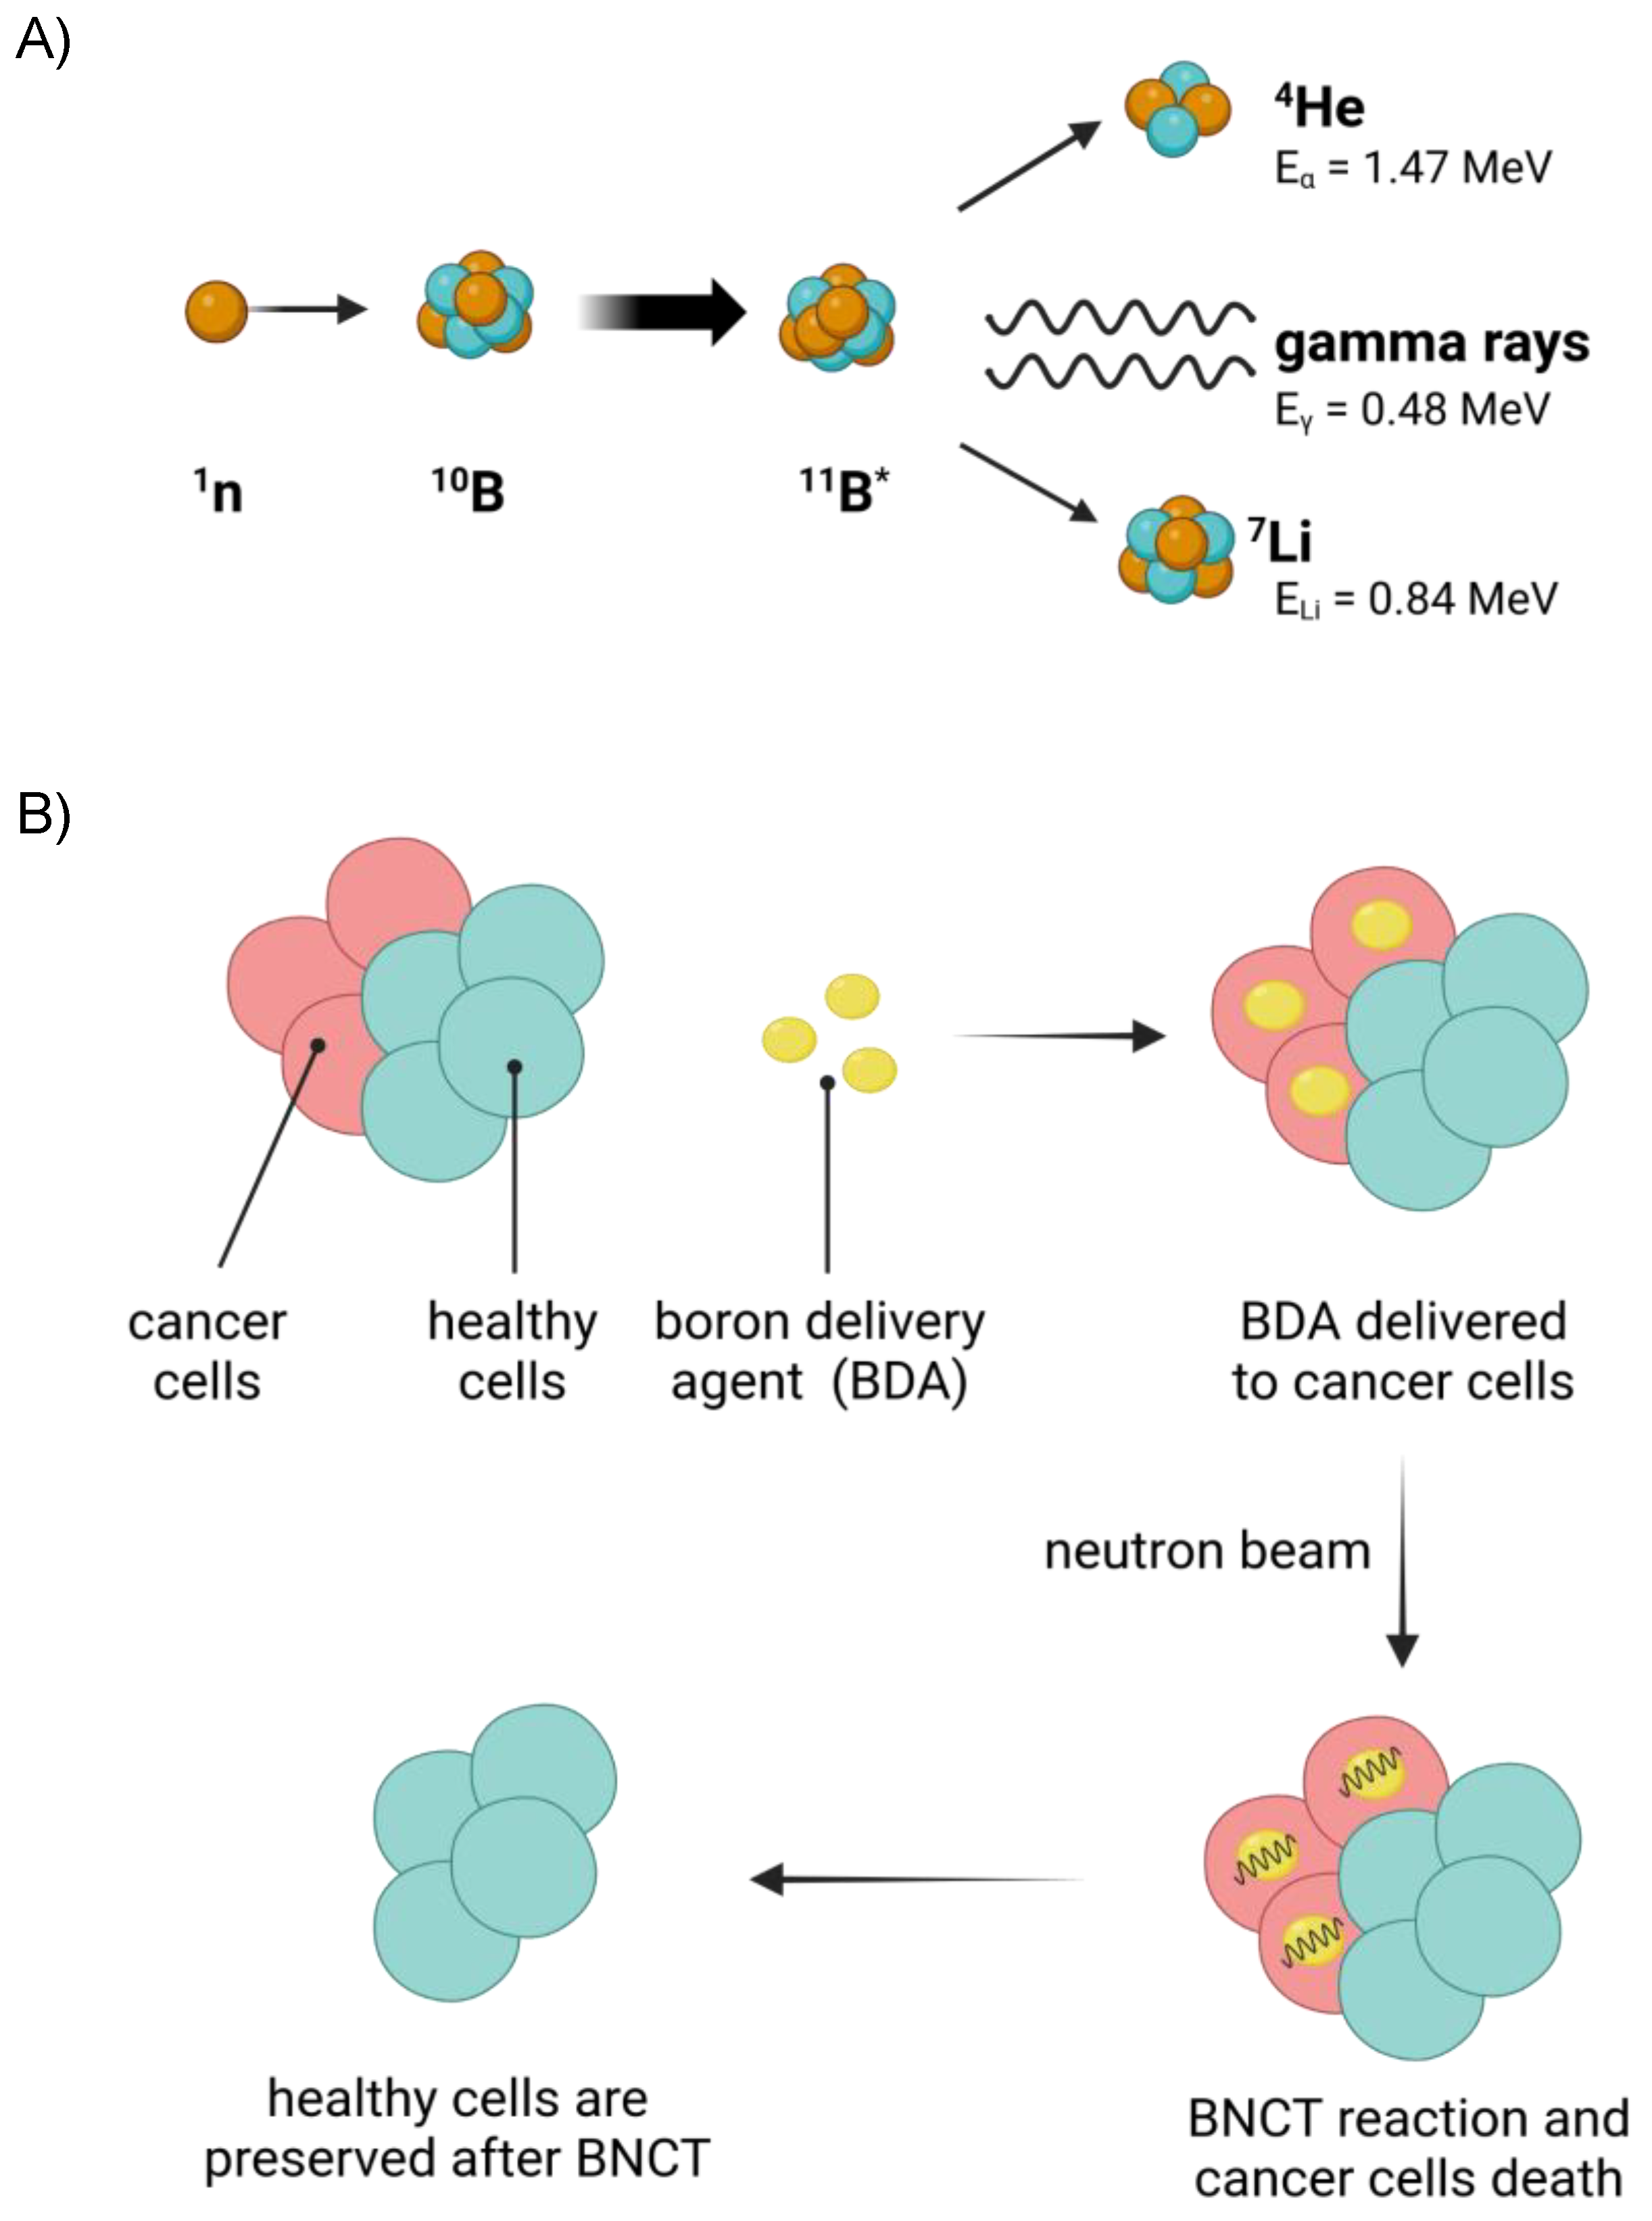

1. Introduction